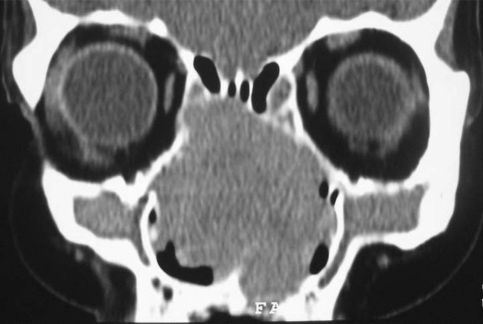

Computed tomography (CT) scan showed 7.5 × 3.5 cm mass filling nasal cavity, frontal and ethmoid sinuses and expanding medial wall of orbita. It caused erosion of septum, partially anterior part of maxillary sinus. Bilateral osteomeatal complexes were obstructed (Fig. 1).

Fig. 1.

Coronal computed tomography (CT) showed large intranasal mass